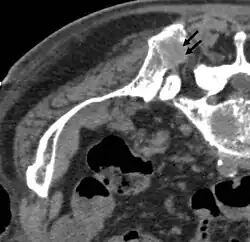

- CT-Aufnahmen einer Hochfrequenzablation (RFA)

-

Vor der RFA: Hinterer oberer Darmbeindorn (Spina iliaca posterior superior) mit osteolytischer Metastase (ca. 2 cm im Durchmesser, siehe Pfeile) -

Während der RFA: A) Die HF-Elektrode wurde direkt in die Knochenmetastase geführt. B) Nach der Ablation wurde eine Mischung aus Knochenzement und Bariumsulfat in den entstandenen Freiraum injiziert. -

Nach der RFA: Die Verteilung des Knochenzementes in dem nach der Ablation entstandenen Hohlraum ist zu erkennen.